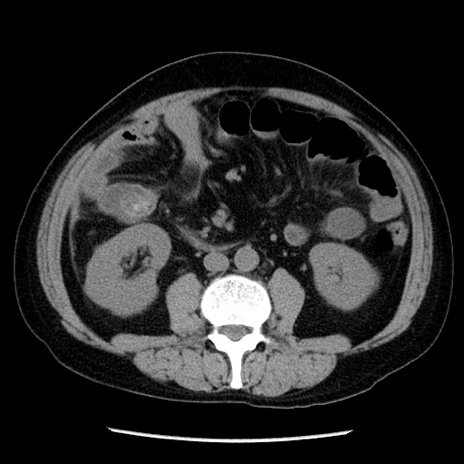

冠状断像

【症例】40歳代男性

【現病歴】2日前から胃痛あり。徐々に周期的な激痛に変化した。本日になっても激痛があるため受診。

【身体所見】意識清明、BT 38-39℃台あり、腹部:膨満、やや硬、右下腹部に圧痛あり。

【データ】WBC 8500、CRP 23.26